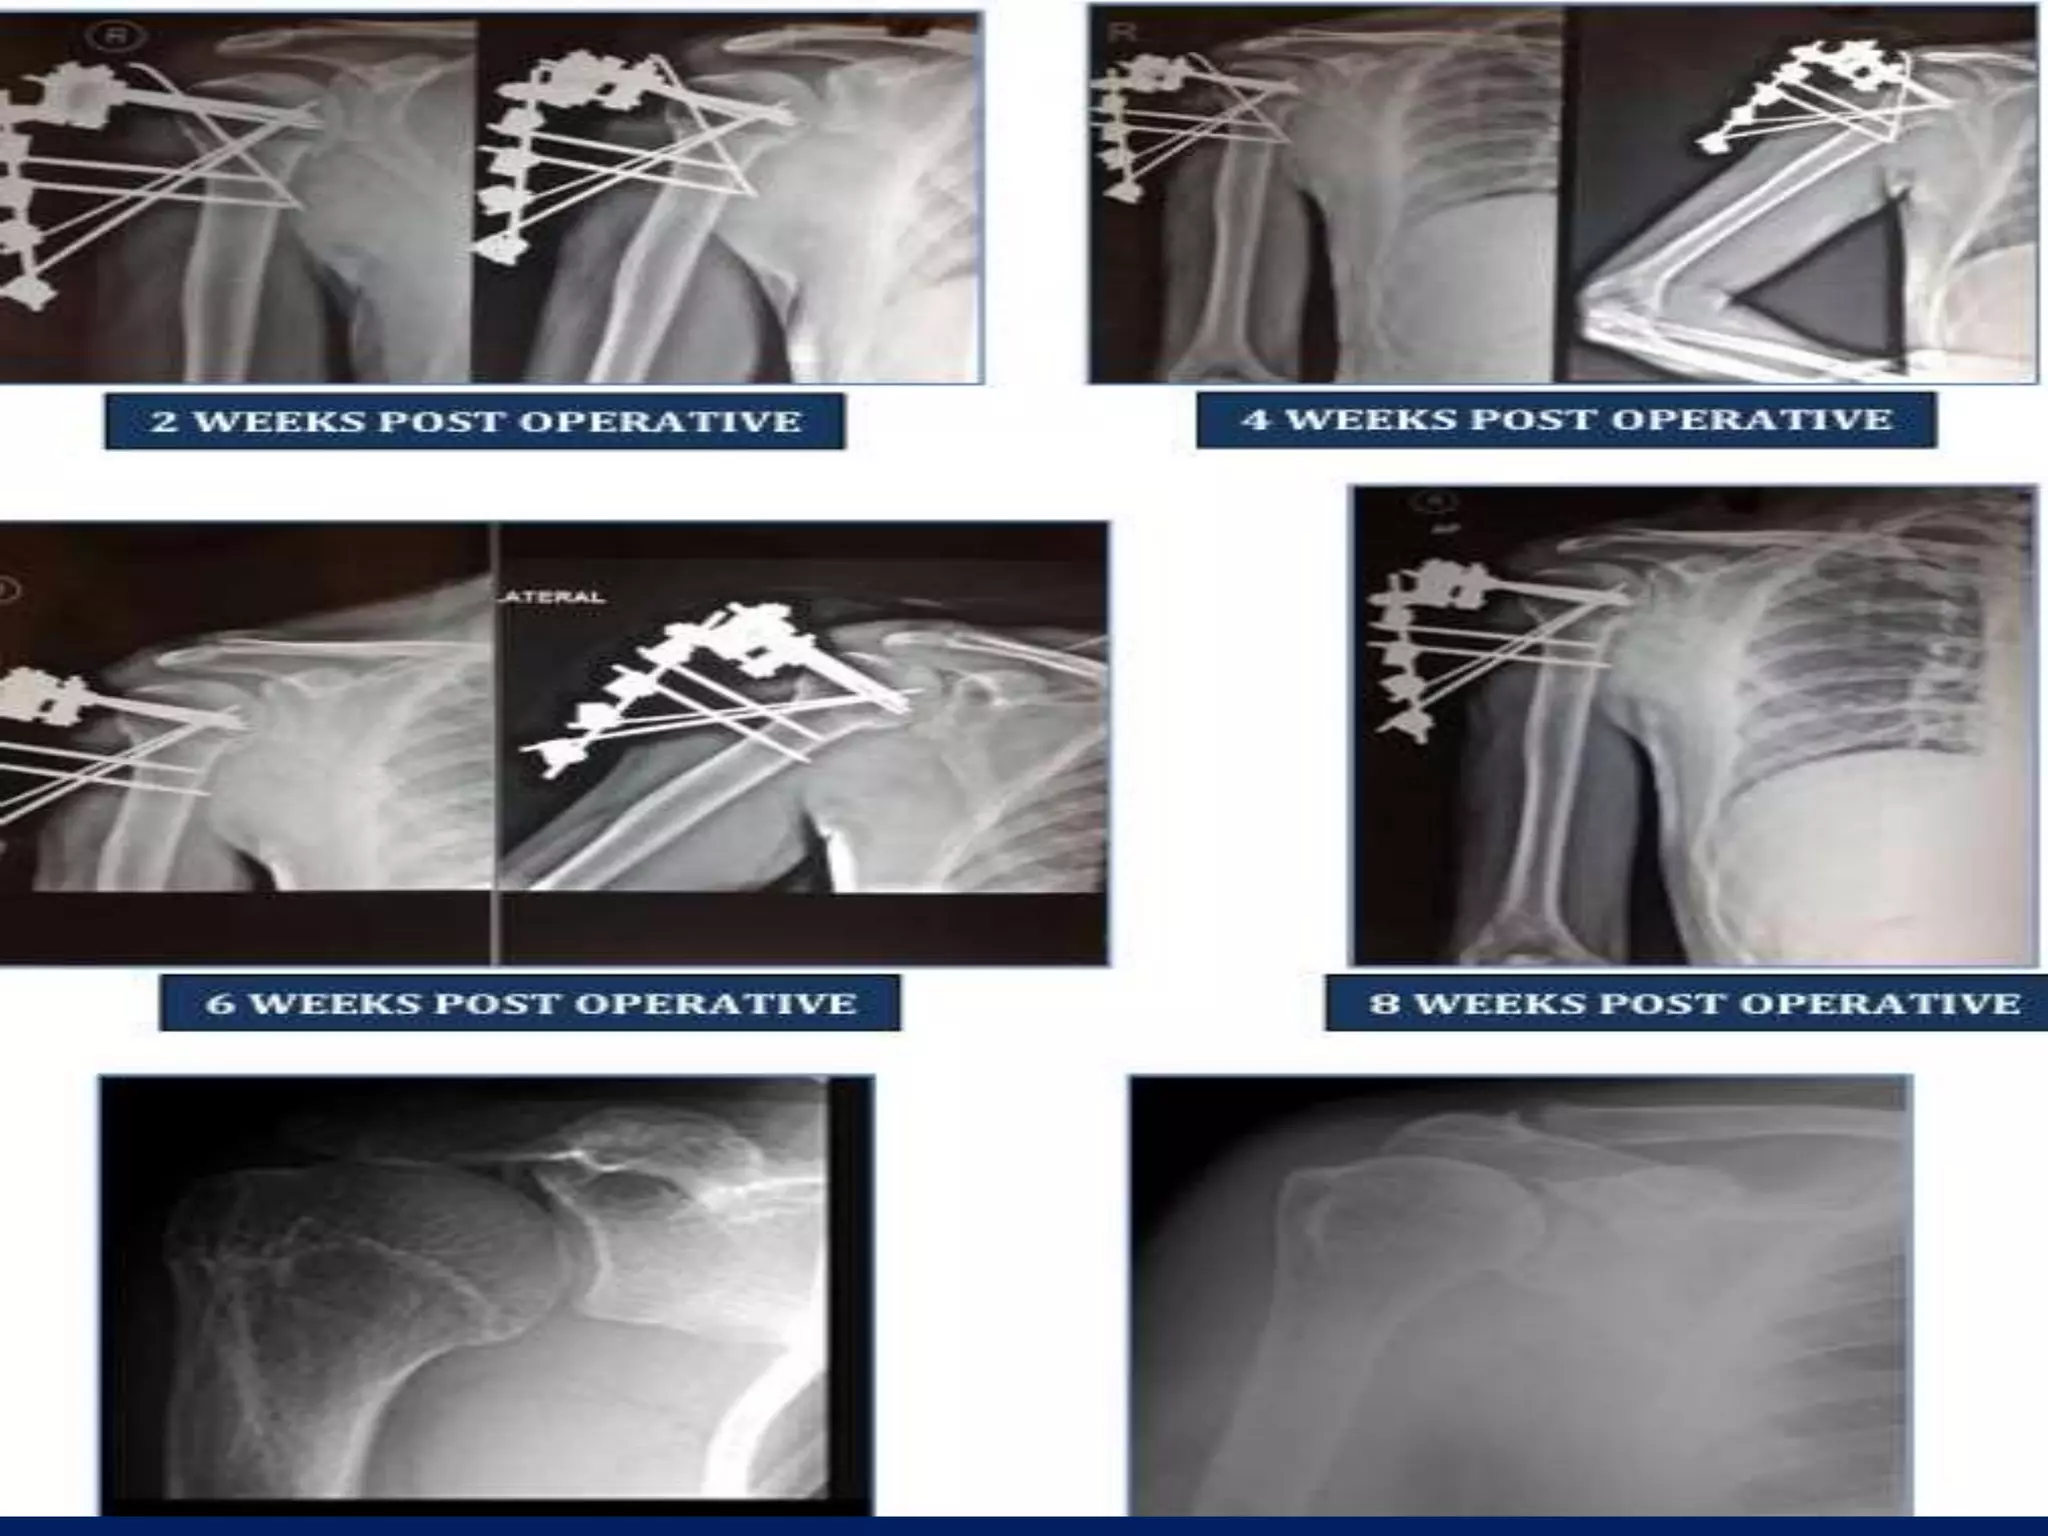

Post op • Poucharm sling is applied. • Pain free ROM, ASAP. • Pins cleaned with Povidone iodine. • Patient follow up for 2,4,6 and 8 weeks. • Removal at 6 or 8 week. • Then for bimonthly till 1 year.

Fracture proximal humerus Fixation with K wires and External fixator